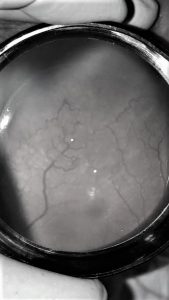

Vascularización incompleta